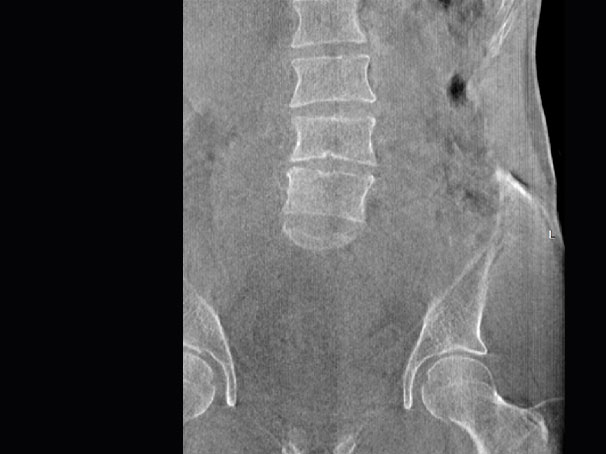

• 腰椎

三维脊柱应用

精准诊断

手术方案规划

术后随访

• 脊柱评估

传统方法都是在二维平面,依靠棘突或椎弓根相对于椎体的偏移来评估脊柱侧凸。WR-3D可以更精准评估脊柱侧凸,制定手术方案,可以更直观地显示和量化椎体的平移和轴向旋转,术后评估更准确客观。

• 全身姿态评估

WR-3D能提供一种负重位状态下全身的姿态和三维空间任一平面平衡评估,使全脊柱术后评价更客观、真实 。通过各种临床参数包括骨盆、脊柱参数评价骨盆、脊柱平衡,避免由于髋膝屈曲造成的代偿性脊柱失衡的发生,WR-3D提供了三维空间任一平面平衡评估测量方法,可以更加定量地评估手术效果 。